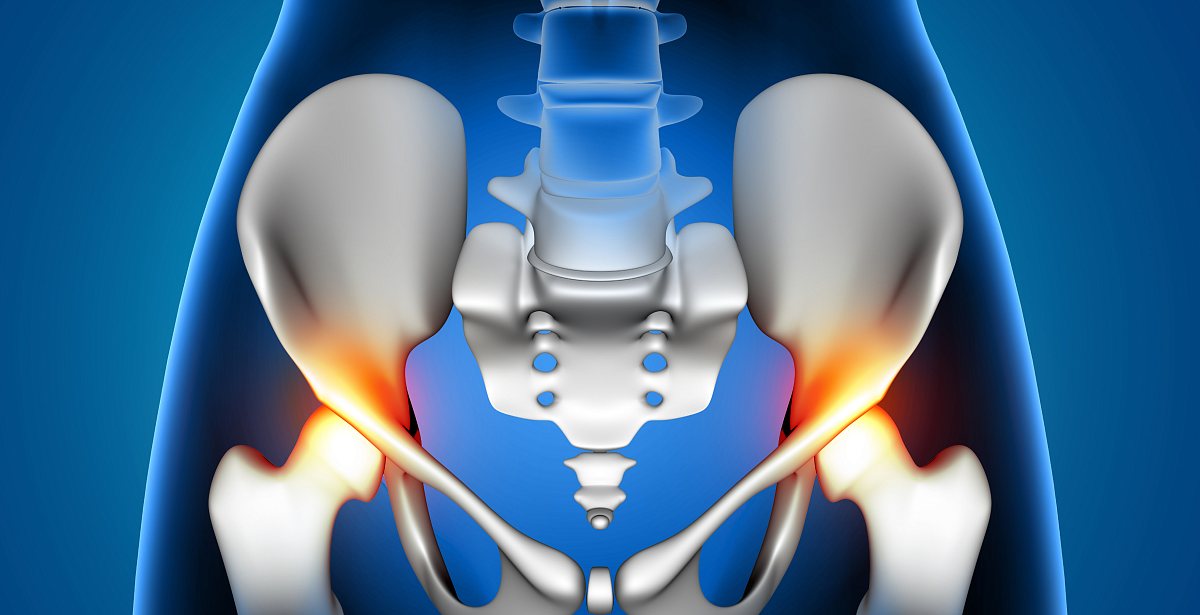

Опытные образцы нового керамического порошка по качеству сопоставимы с продукцией ведущих мировых производителей, которые применяются для изготовления эндопротезов, подверженных интенсивной нагрузке, — тазобедренных и коленных суставов. Благодаря высокой износостойкости срок службы керамического импланта достигает 20 лет — в отличие от металлического аналога.Перспективы